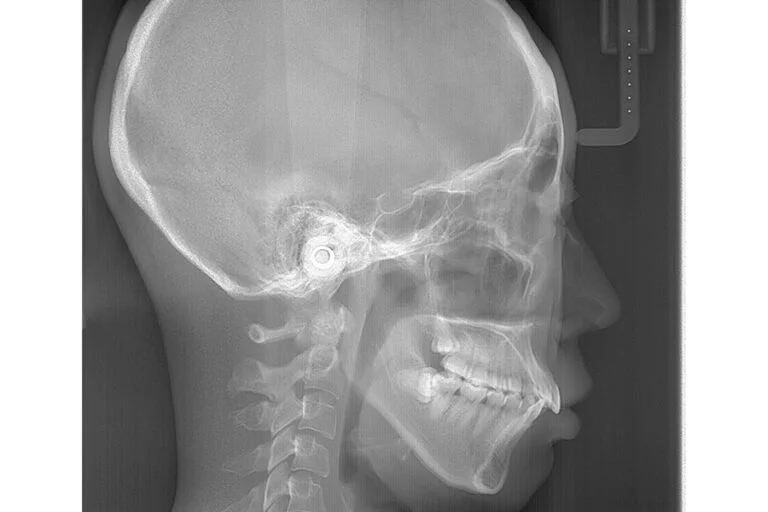

頭部X線規格写真

(セファログラム)

セファログラムは矯正治療で非常に重要とされる検査の一つです。

歯科医院でレントゲンを撮影する場合、通常は歯全体と上下のあごが撮影対象となりますが、セファロレントゲンでは頭部全体を正面と横から撮影します。

これにより、歯やあごの状態の確認だけでなく、頭に対してあごの大きさや位置・上下のあごの位置関係・歯とあごの位置関係など、様々なデータを得ることが可能となります。得られたデータを元に最適な治療計画を立てていきます。

また、経年的に撮影することで矯正治療前と後の比較や経過観察にも有用です。